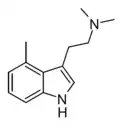

| 4-Methyl-DMT | artificial | 4-CH3 | CH3 | CH3 | 4,N,N-trimethyltryptamine | 28289-23-8 |